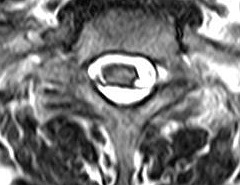

ГМ. СМ. Нейросаркоидоз. Саркоидоз на спинальном уровне. +

Саркоидоз на спинальном уровне.

journal_logo.jpgf24.largespinnogo_mozga_v_23-letniy_muzhchina.jpgf25.mediumspinnogo_mozga_v_23-letniy_muzhchina.giff26.mediumspinnogo_mozga_v_23-letniy_muzhchina.gif